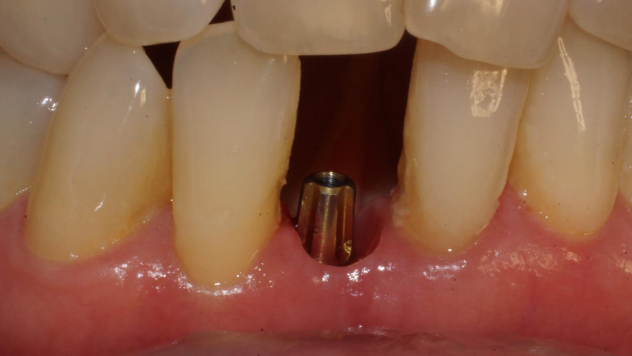

Após 35 dias da instalação do implante foi realizada a abertura do implante através de um bisturi circular e o pilar Ideale reto de 3.3 X 4.0 X 2.5 mm foi torqueado no implante a 20 Ncm. Foi realizada também uma moldagem deste pilar com o seu transferente correspondente e a prótese adesiva voltou a ser instalada. Depois de uma semana, o provisório parafusado confeccionado no laboratório foi instalado e mantido em posição durante 15 dias para formar um novo perfil de emergência, aproximando as características dos tecidos circundantes às características de um incisivo central inferior. Neste momento, foi realizada uma nova moldagem da região e uma coroa metalocerâmica foi confeccionada e instalada após uma semana. Foi também realizada a radiografia.